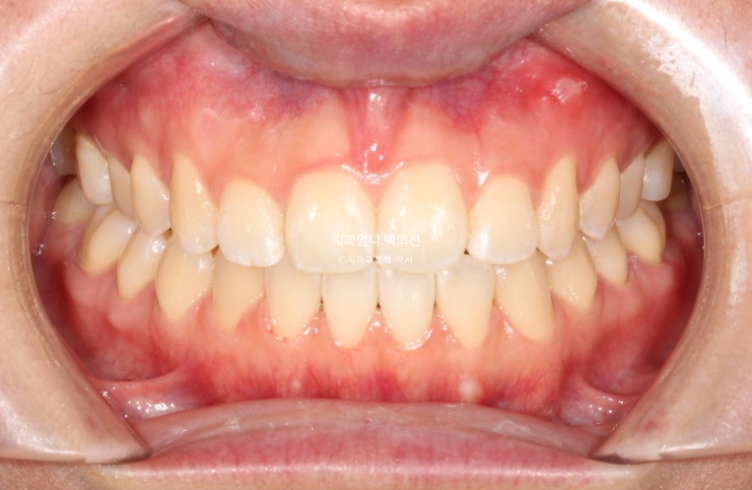

25.06

맞아진 앞니 높낮이와 적절한 앞니 교합

앞니 개방교합이 깔끔하게 해결되었습니다.

이제 전후 비교 보겠습니다.